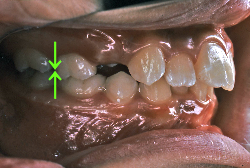

「ものがうまく噛めない」という主訴で来院したケースです。診断の結果、「骨格性反対咬合に伴う咬合不良+軽度叢生」と判明しました。原因としては特に下顎の左側が過成長したため、骨格性反対咬合になり、特に左側での噛み合わせが非常に悪くなっていると診断しました。初診時の写真を見ると、上下の正中線の大きなズレ、左側の噛み合わせの不良がはっきり分かります(黄色の矢印と緑の矢印は一致しているのが正しい状態です)。